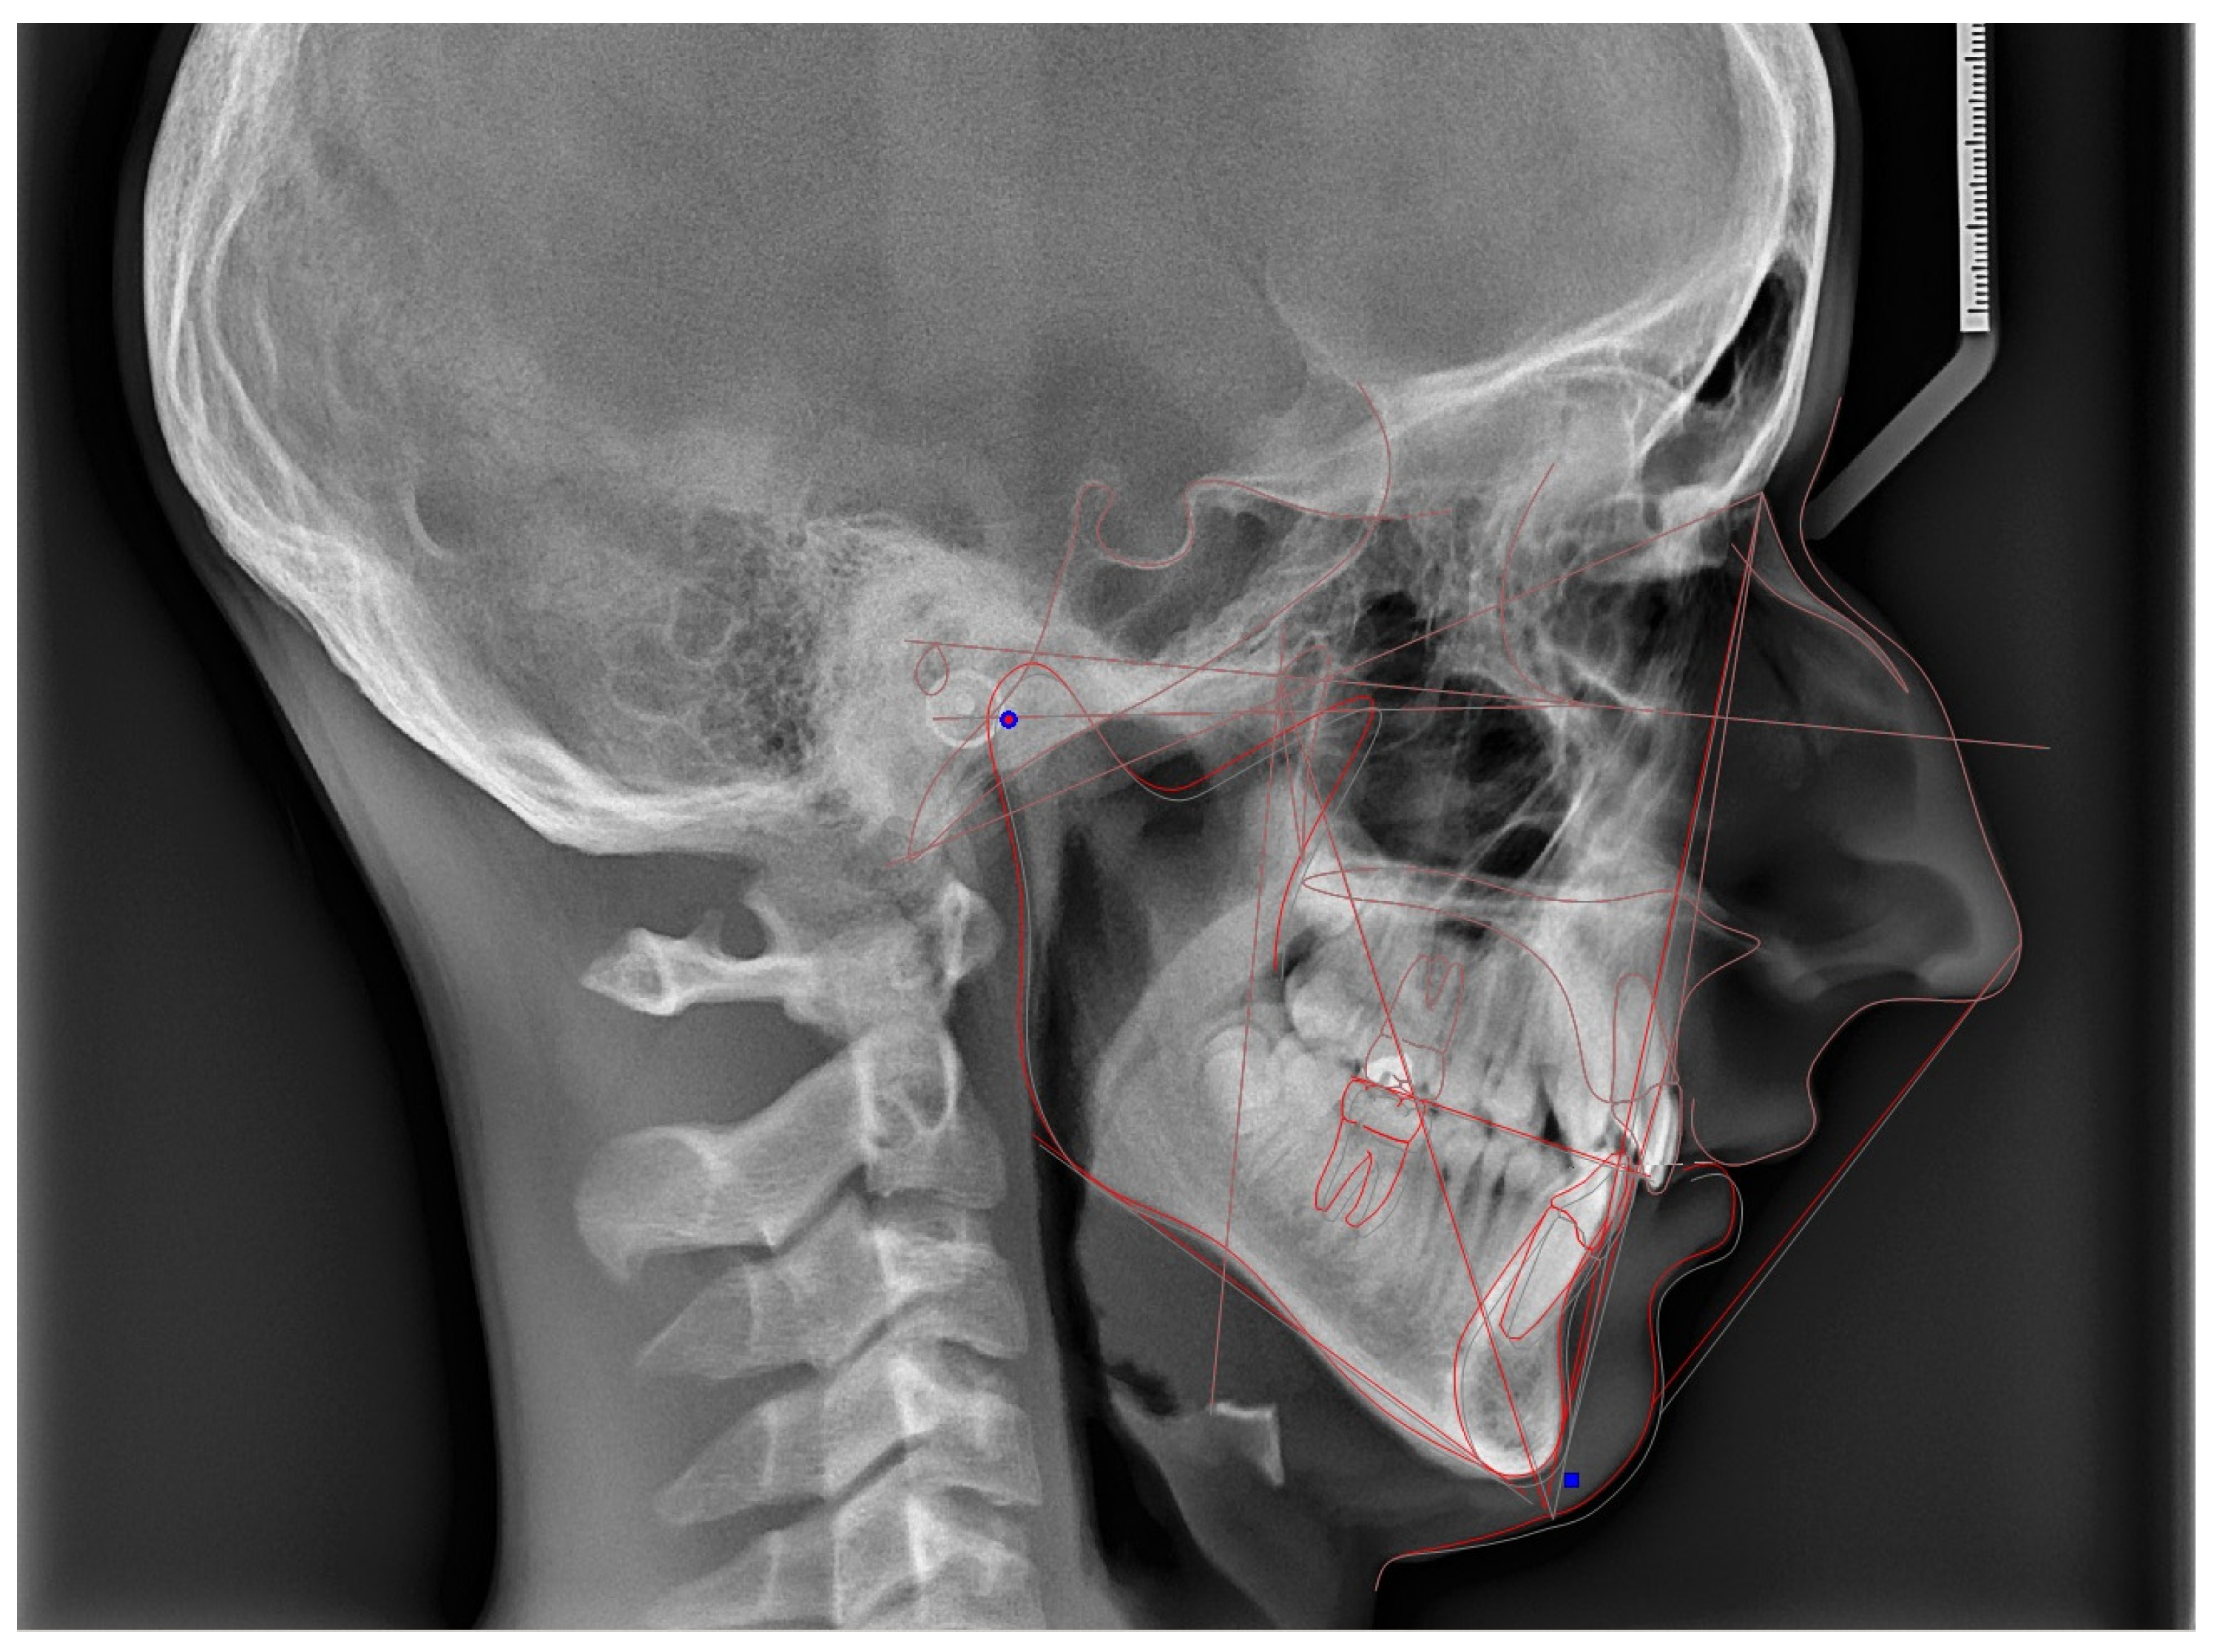

2.4. Cephalometric Analysis

3.2.2. Cephalometric Variables